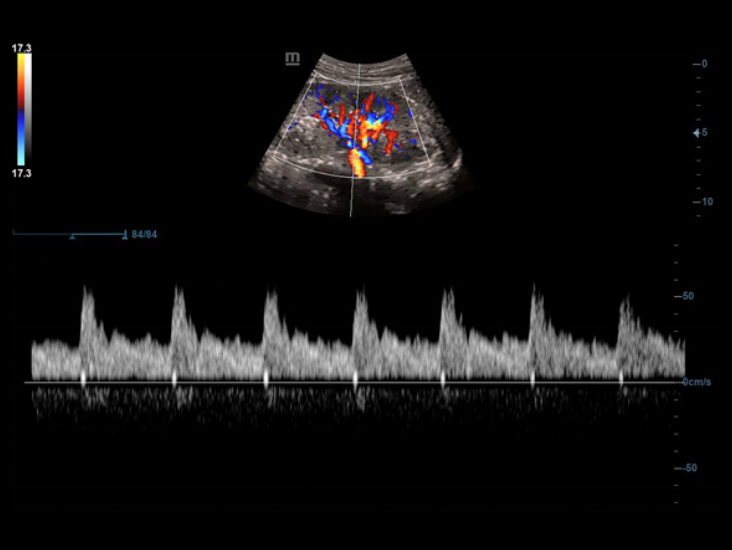

Smart Track

Smart Track proporciona una optimizaciĂłn rĂĄpida e inteligente de imĂĄgenes vasculares con un sencillo manejo de un solo toque. Puede optimizar el espectro de Color, Potencia y PW mediante seguimiento automĂĄtico y reducir los pasos que llevan tiempo. Por lo tanto, el flujo de trabajo del examen vascular se simplifica con una Ăłptima visualizaciĂłn.